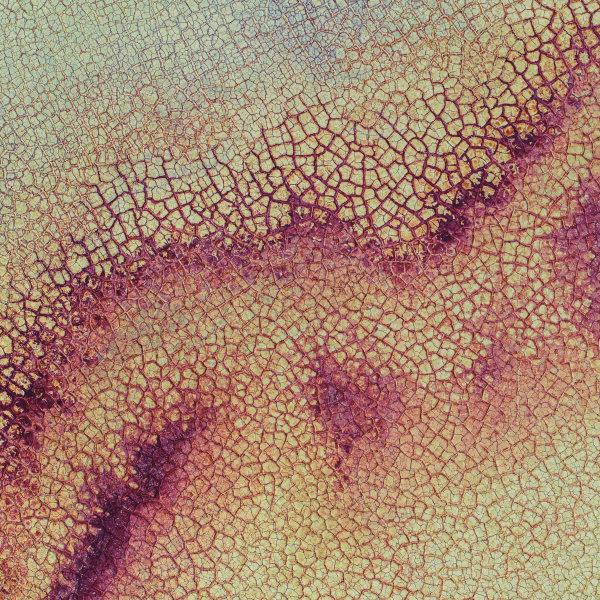

.png)

Endocrine and Hormonal Disorders

Acromegaly stems from excess growth hormone, causing tissue overgrowth and metabolic strain. Blood testing—especially IGF‑1—confirms abnormal hormone activity and guides evaluation. At Superpower, we offer IGF‑1 testing for acromegaly in‑clinic and at home. Home blood testing is currently available in selected states. (See FAQs below for more info).

Blood testing helps confirm Addison’s disease early by revealing low cortisol and disrupted salt balance. At Superpower, we test Cortisol, Sodium, and Potassium to assess adrenal function (hypocortisolism, hyponatremia, hyperkalemia). We offer in-clinic and at-home testing. Home testing is available in selected states. (See FAQs below for more info).

Blood testing helps confirm Cushing’s syndrome by revealing excess adrenal hormone activity—elevated cortisol and androgen pathway signals (DHEAS). At Superpower, we offer cortisol and DHEAS testing for Cushing’s, with both in-clinic and at-home options. Home testing is currently available in selected states. (See FAQs below for more info).

Blood testing can uncover growth hormone problems by tracking the body’s GH effect over time. IGF-1 (insulin-like growth factor 1) reflects average GH activity. At Superpower, we offer IGF-1 testing for GH deficiency in-clinic and at home; home testing is available in selected states. (See FAQs below for more info).

Blood testing clarifies thyroid autoimmunity and hormone balance in Hashimoto’s, capturing immune antibodies and pituitary-thyroid signaling. Superpower offers TPO Ab, Tg Ab, TSH, and Free T4 testing, with in-clinic and at-home options. Home testing for Hashimoto’s is currently available in selected states. (See FAQs below for more info).